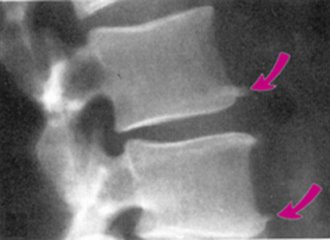

前面我们也介绍过骨刺的发生原因和产生机理。骨刺(骨赘)是人的机体对于应力、磨损、炎症等的一种反应,通过这种适应性反应,可以起到稳定局部环境,维持机体的功能,从这个角度上说,骨刺是一种正常的代偿反应,并非多余。

虽然骨刺是医生诊断骨性关节炎的一个依据,但绝大多数不是引起局部疼痛的真正原因,更不是它直接引起疼痛症状。只有当局部的骨刺对周围的软策划产生顶压等刺激时,才会引起局部的疼痛症状,并且这种情况非常少见。

导致关节疼痛的主要原因是关节软骨损伤、半月板磨损、关节力线改变等。因而相应的治疗需要在准确把握病因的基础上治疗才是正确的选择。